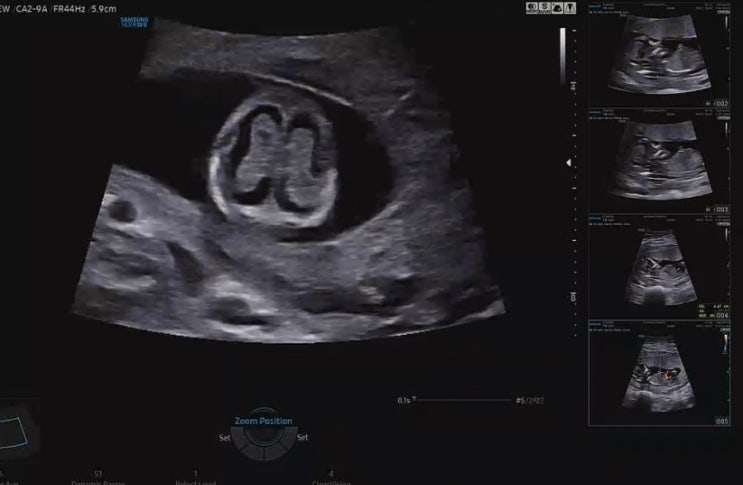

임신 중기 24주 5일 임당검사 및 정밀초음파

안녕하세요 별이맘스리입니다 지난 검진 다녀오면서 이번에 방문 할 때는 “임당 검사”가 포함되어 있다고...